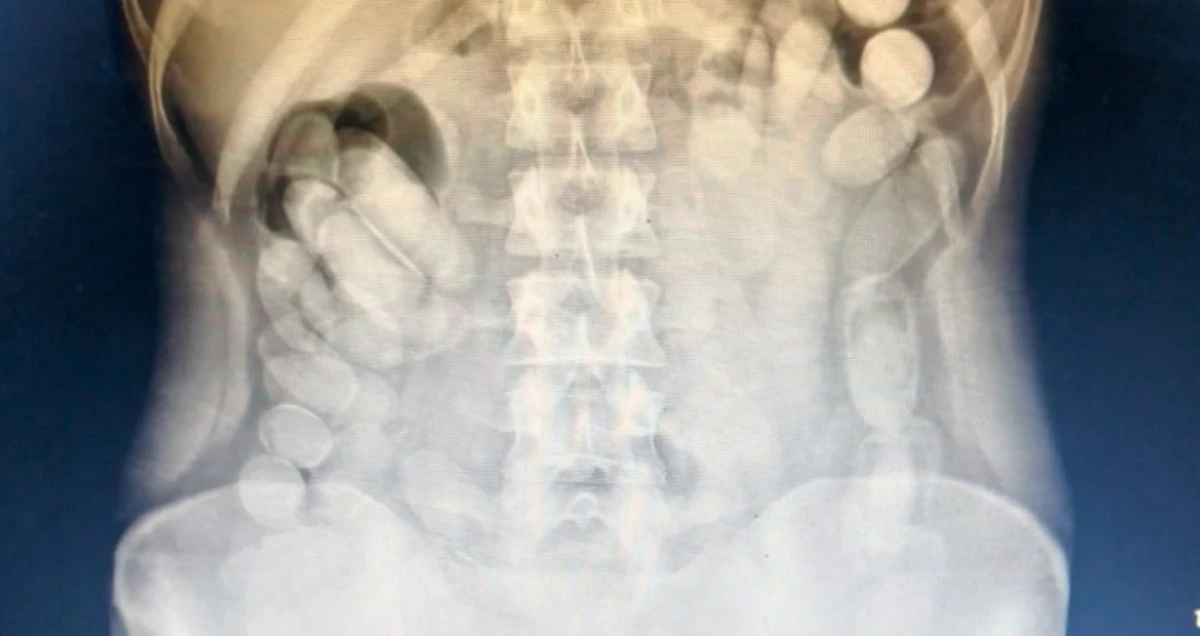

Allí se le practicó una radiografía que confirmó la presencia de decenas de cápsulas en su abdomen. Luego, la mujer evacuó un total de 106 envoltorios adicionales. En total, se secuestraron 118 cápsulas que, sometidas a pruebas de campo (Narcotest), arrojaron resultado positivo para cocaína, con un peso final de 1 kilo 388 gramos.